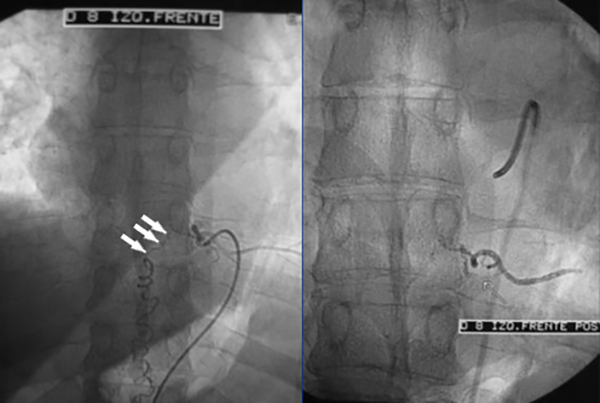

Figura 5: Caso #1. ADM mostrando la FDAVE en D8 izq. antes y después de la embolización. En la imagen de la izquierda (pre-embolización) las flechas blancas muestran la vena de drenaje de la FDAVE desde el punto fistuloso (más lateral) hacia medial en forma descendente y llegando a la línea media en donde se anastomosa con la vena espinal posterior y continúa hacia abajo en forma serpiginosa. La foto de la derecha (post-embolización) dejó de observarse la vena de drenaje y la vena espinal posterior (oclusión total de la FDAVE).

CASO #1. Paciente masculino de 52 años con una historia de 6 meses de evolución de disestesias en ambos miembros inferiores, inestabilidad en la marcha, hiperreflexia y urgencia miccional. Se estudió con RMN (Fig. 3), ARM (Fig. 4) y ADM seguida de embolización con oclusión total de una FDAVE D8 izq. (Fig. 5). Evolucionó sin déficit y a los 11 meses comenzó con la misma sintomatología previa a la embolización. Se estudió nuevamente y la ADM (Fig. 6) mostraba la recidiva de la FDAVE y fue derivada para microcirugía (Fig. 7). Luego de la cirugía evolucionó sin déficit, se realizó una ADM diferida (Fig. 8) y lleva 116 meses libres de enfermedad.